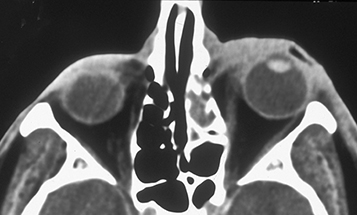

Perform CT scan of the orbits and sinuses (axial and coronal views) with contrast if there is a history of significant trauma or a concern for orbital or intraocular foreign body, orbital cellulitis, subperiosteal abscess, paranasal sinusitis, cavernous sinus thrombosis, or malignancy. Consider MRI or angiographic imaging if cavernous sinus or intracranial pathology.